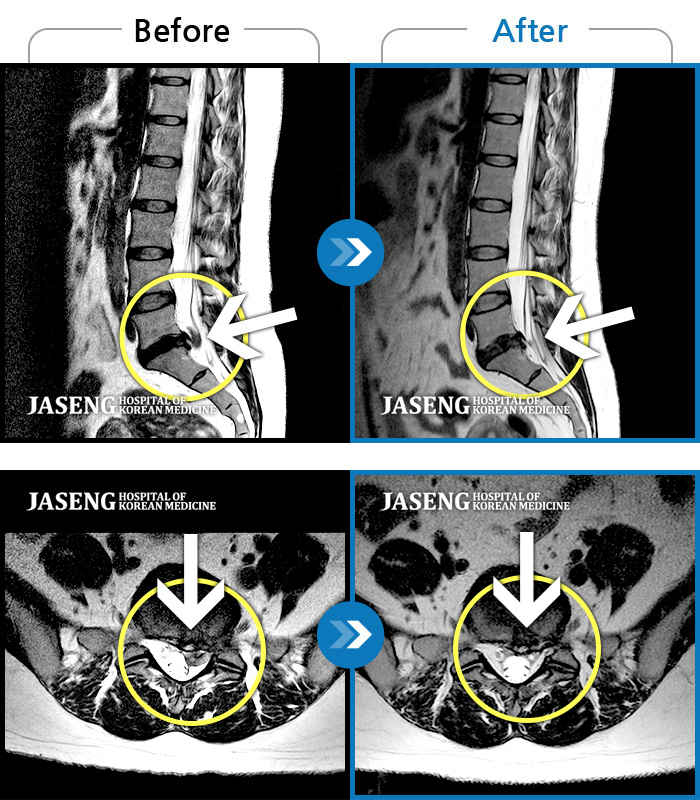

허리디스크

강남 · 박종훈 원장

허리와 양쪽 엉덩이 통증 및 좌측 둔부, 대퇴, 소퇴 후면부 통증 및 저림

촬영시기

2013.05.14 ~ 2014.04.23

2014.05.07